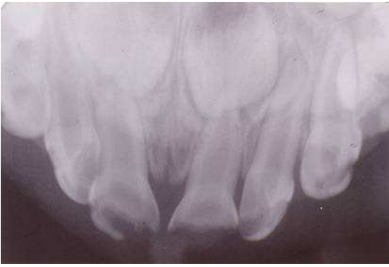

35.有位3歲女孩,患有齲齒及上顎門牙牙冠折斷(crown fracture)伴隨牙髓暴露,臨床並無其他症狀,其X光 如圖,就左側正中門牙而言,下列何者不是合理的處理? (A)拔除 (B)冠髓切除術(pulpotomy) (C)追蹤觀察即可 (D)根管治療(root canal therapy)